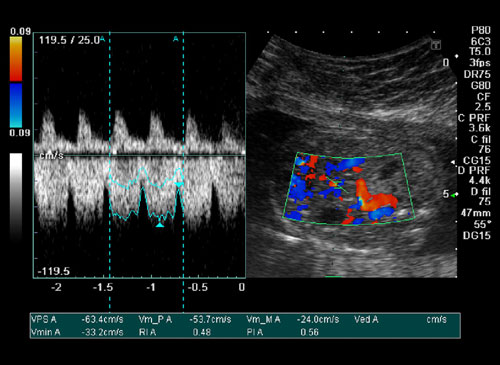

Doppler

Doppler ultrasound is a noninvasive test that can be used to estimate your blood flow through blood vessels. This test may be done as an alternative to more invasive procedures, such as arteriography and venography, which involve injecting dye into the blood vessels so that they show up clearly on X-ray images. It is very helpful to diagnose blood clots, poorly functioning valves in your leg veins, a blocked artery, decreased blood circulation into your legs (peripheral artery disease), narrowing of an artery, such as in your neck (carotid artery stenosis) esp. in patients coming with stroke in the hospital.